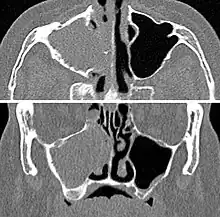

MRI image showing sinusitis. Edema and mucosal thickening appears in both maxillary sinuses. -

Maxillary sinusitis caused by a dental infection associated with periorbital cellulitis -